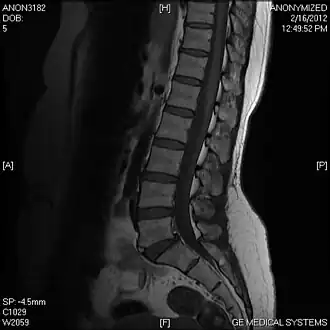

In der Radiologie und besonders der tomographischen Bildgebung spielen Sagittalschnitte als in einer Sagittalebene aufgenommene oder rekonstruierte Bilddaten eine wichtige Rolle. Aus der tomographischen Untersuchung solcher Ebenen ergeben sich die sagittalen Schichtungen, die den Körper eines untersuchten Patienten so darstellen, dass sich von der einen zur anderen Seite aufeinanderfolgende Schichten betrachten lassen.[4]

Sagittalschnitte werden auch bei der Ultraschallmessung beispielsweise der Nackentransparenz im Rahmen der Pränataldiagnostik oder zur Darstellung der Wirbelsäule mit der Magnetresonanztomographie (MRT) oder der Computertomographie (CT) angewendet.